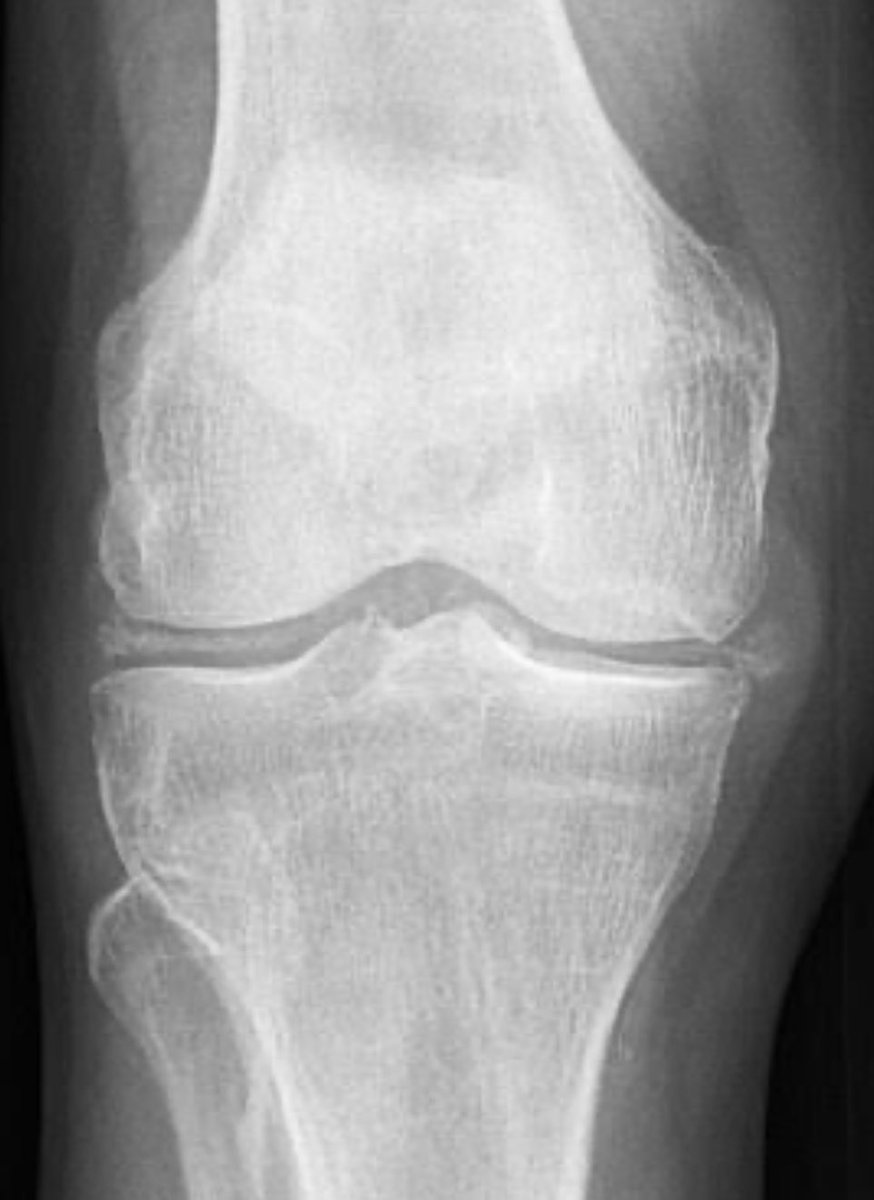

Not all mechanical knee pains are untreatable some just need xray… When the patient walks in with mechanical knee pain, you think 🤔 “Osteoarthritis.” You order X-ray… 🤯🤯 those linear white calcifications staring back at you…. Not OA. Not aging. And the best part??? You can still fix their pain with colchicine. Tell me what you are seeing ???